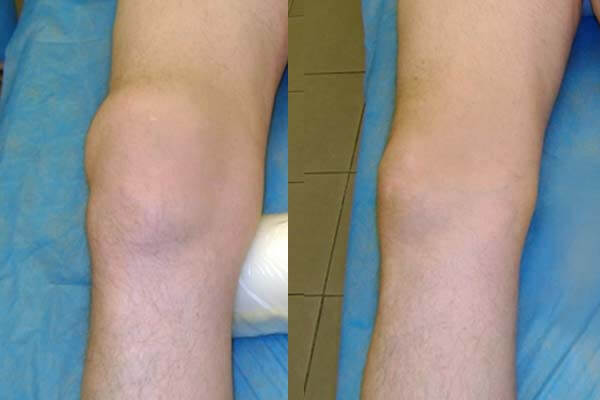

รูปภาพ: ภาพรังสีเอกซ์ของข้อเข่าก่อนและหลังทานแคปซูล Movinix

ผลลัพธ์การรักษาข้อเข่า